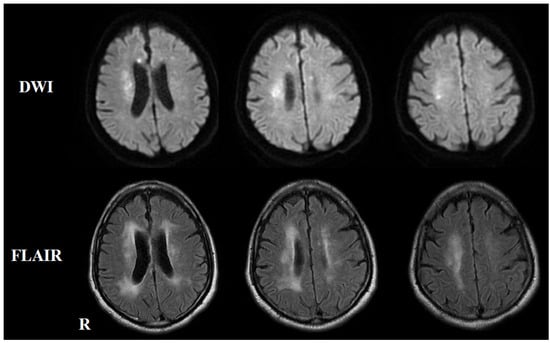

2. Case Presentation